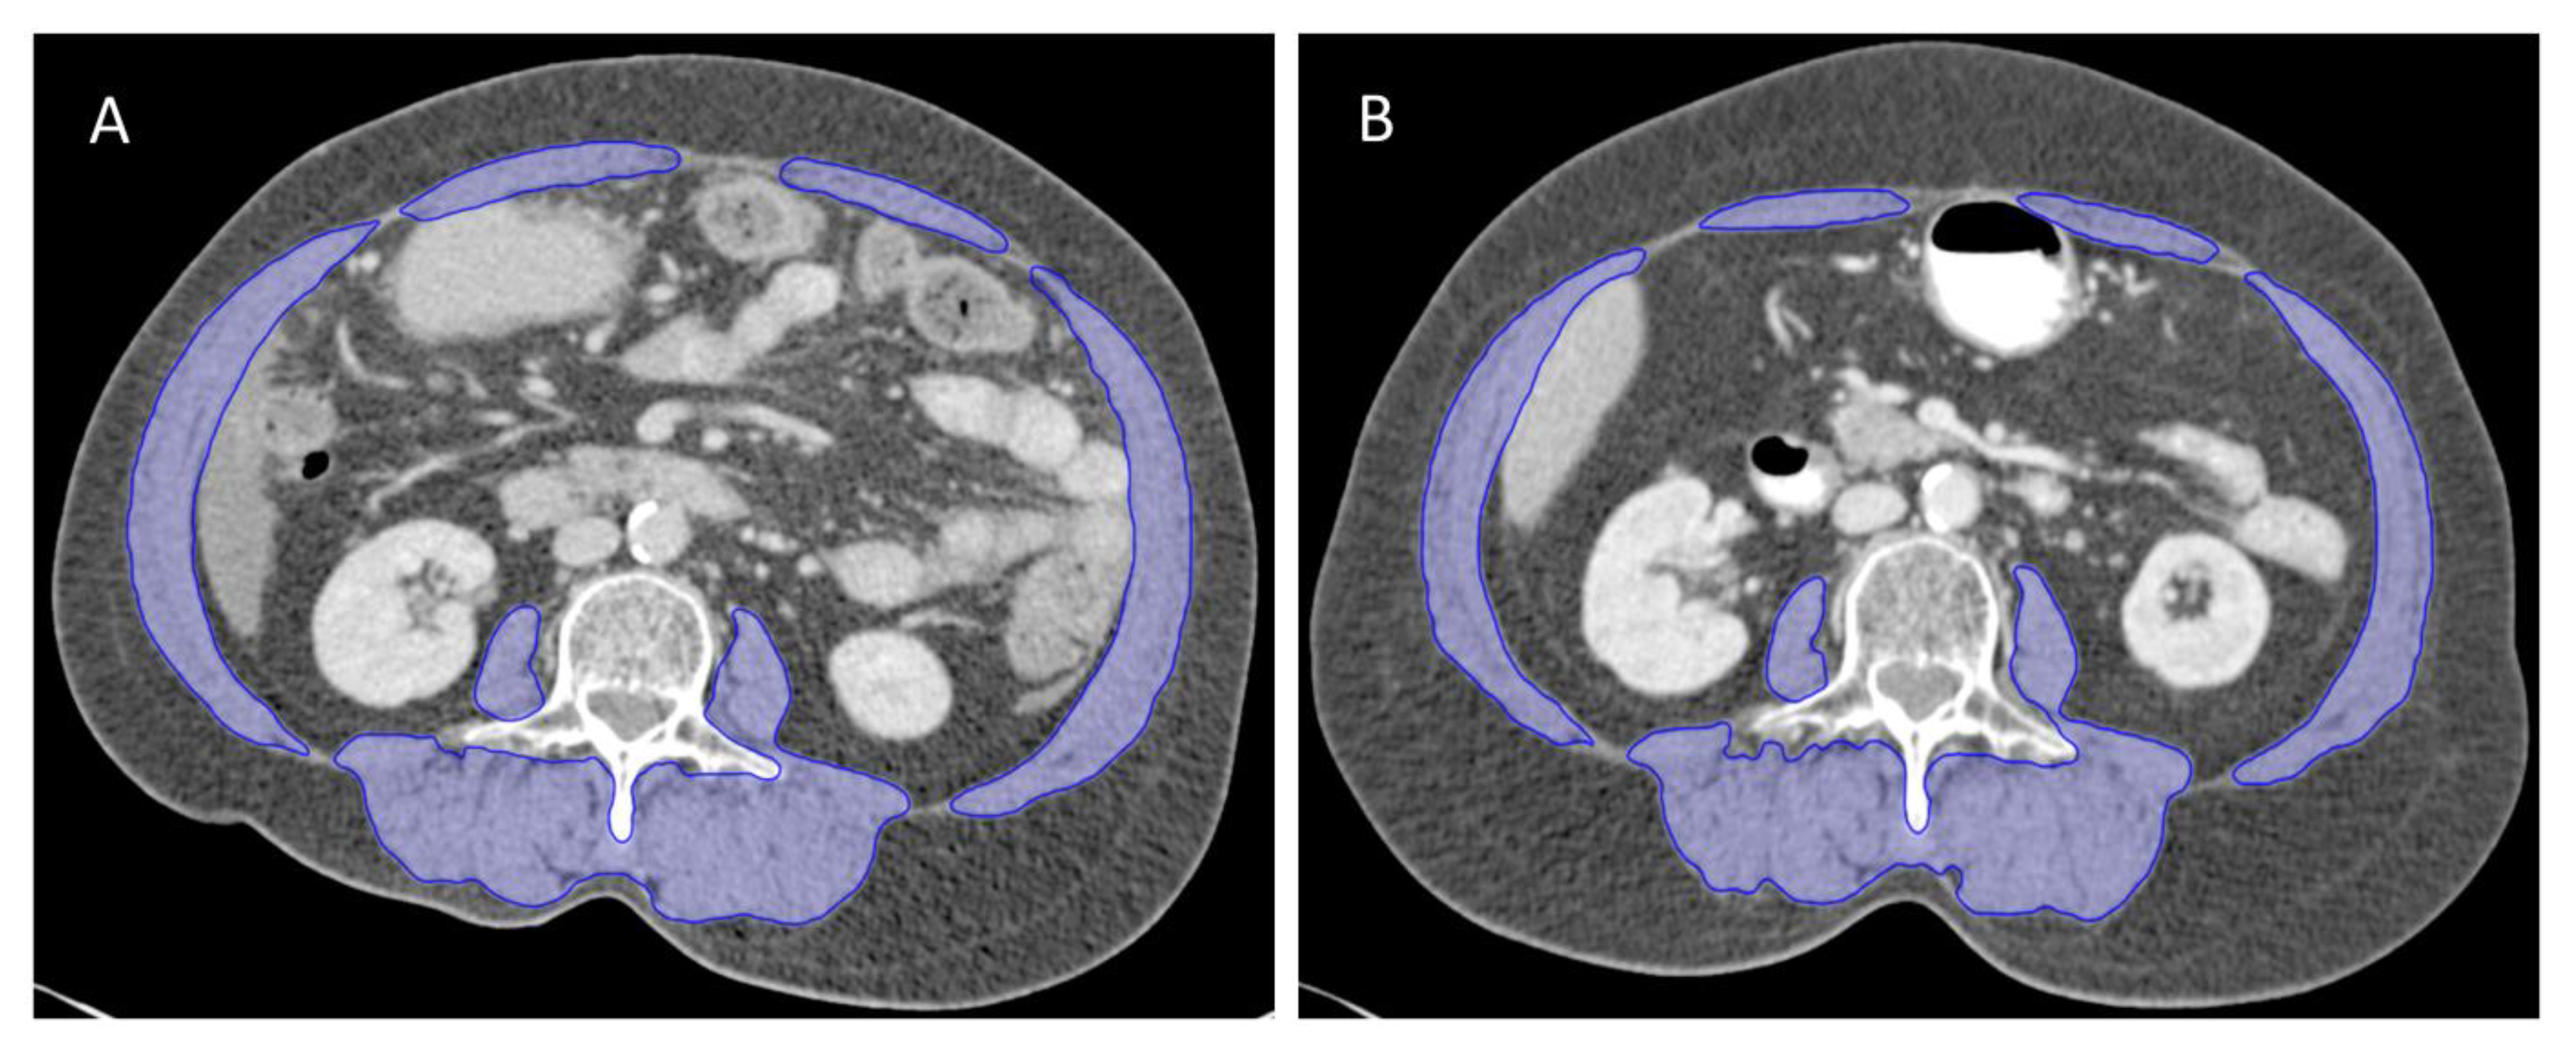

4.2. Computed Tomography-Based Body Composition Analysis